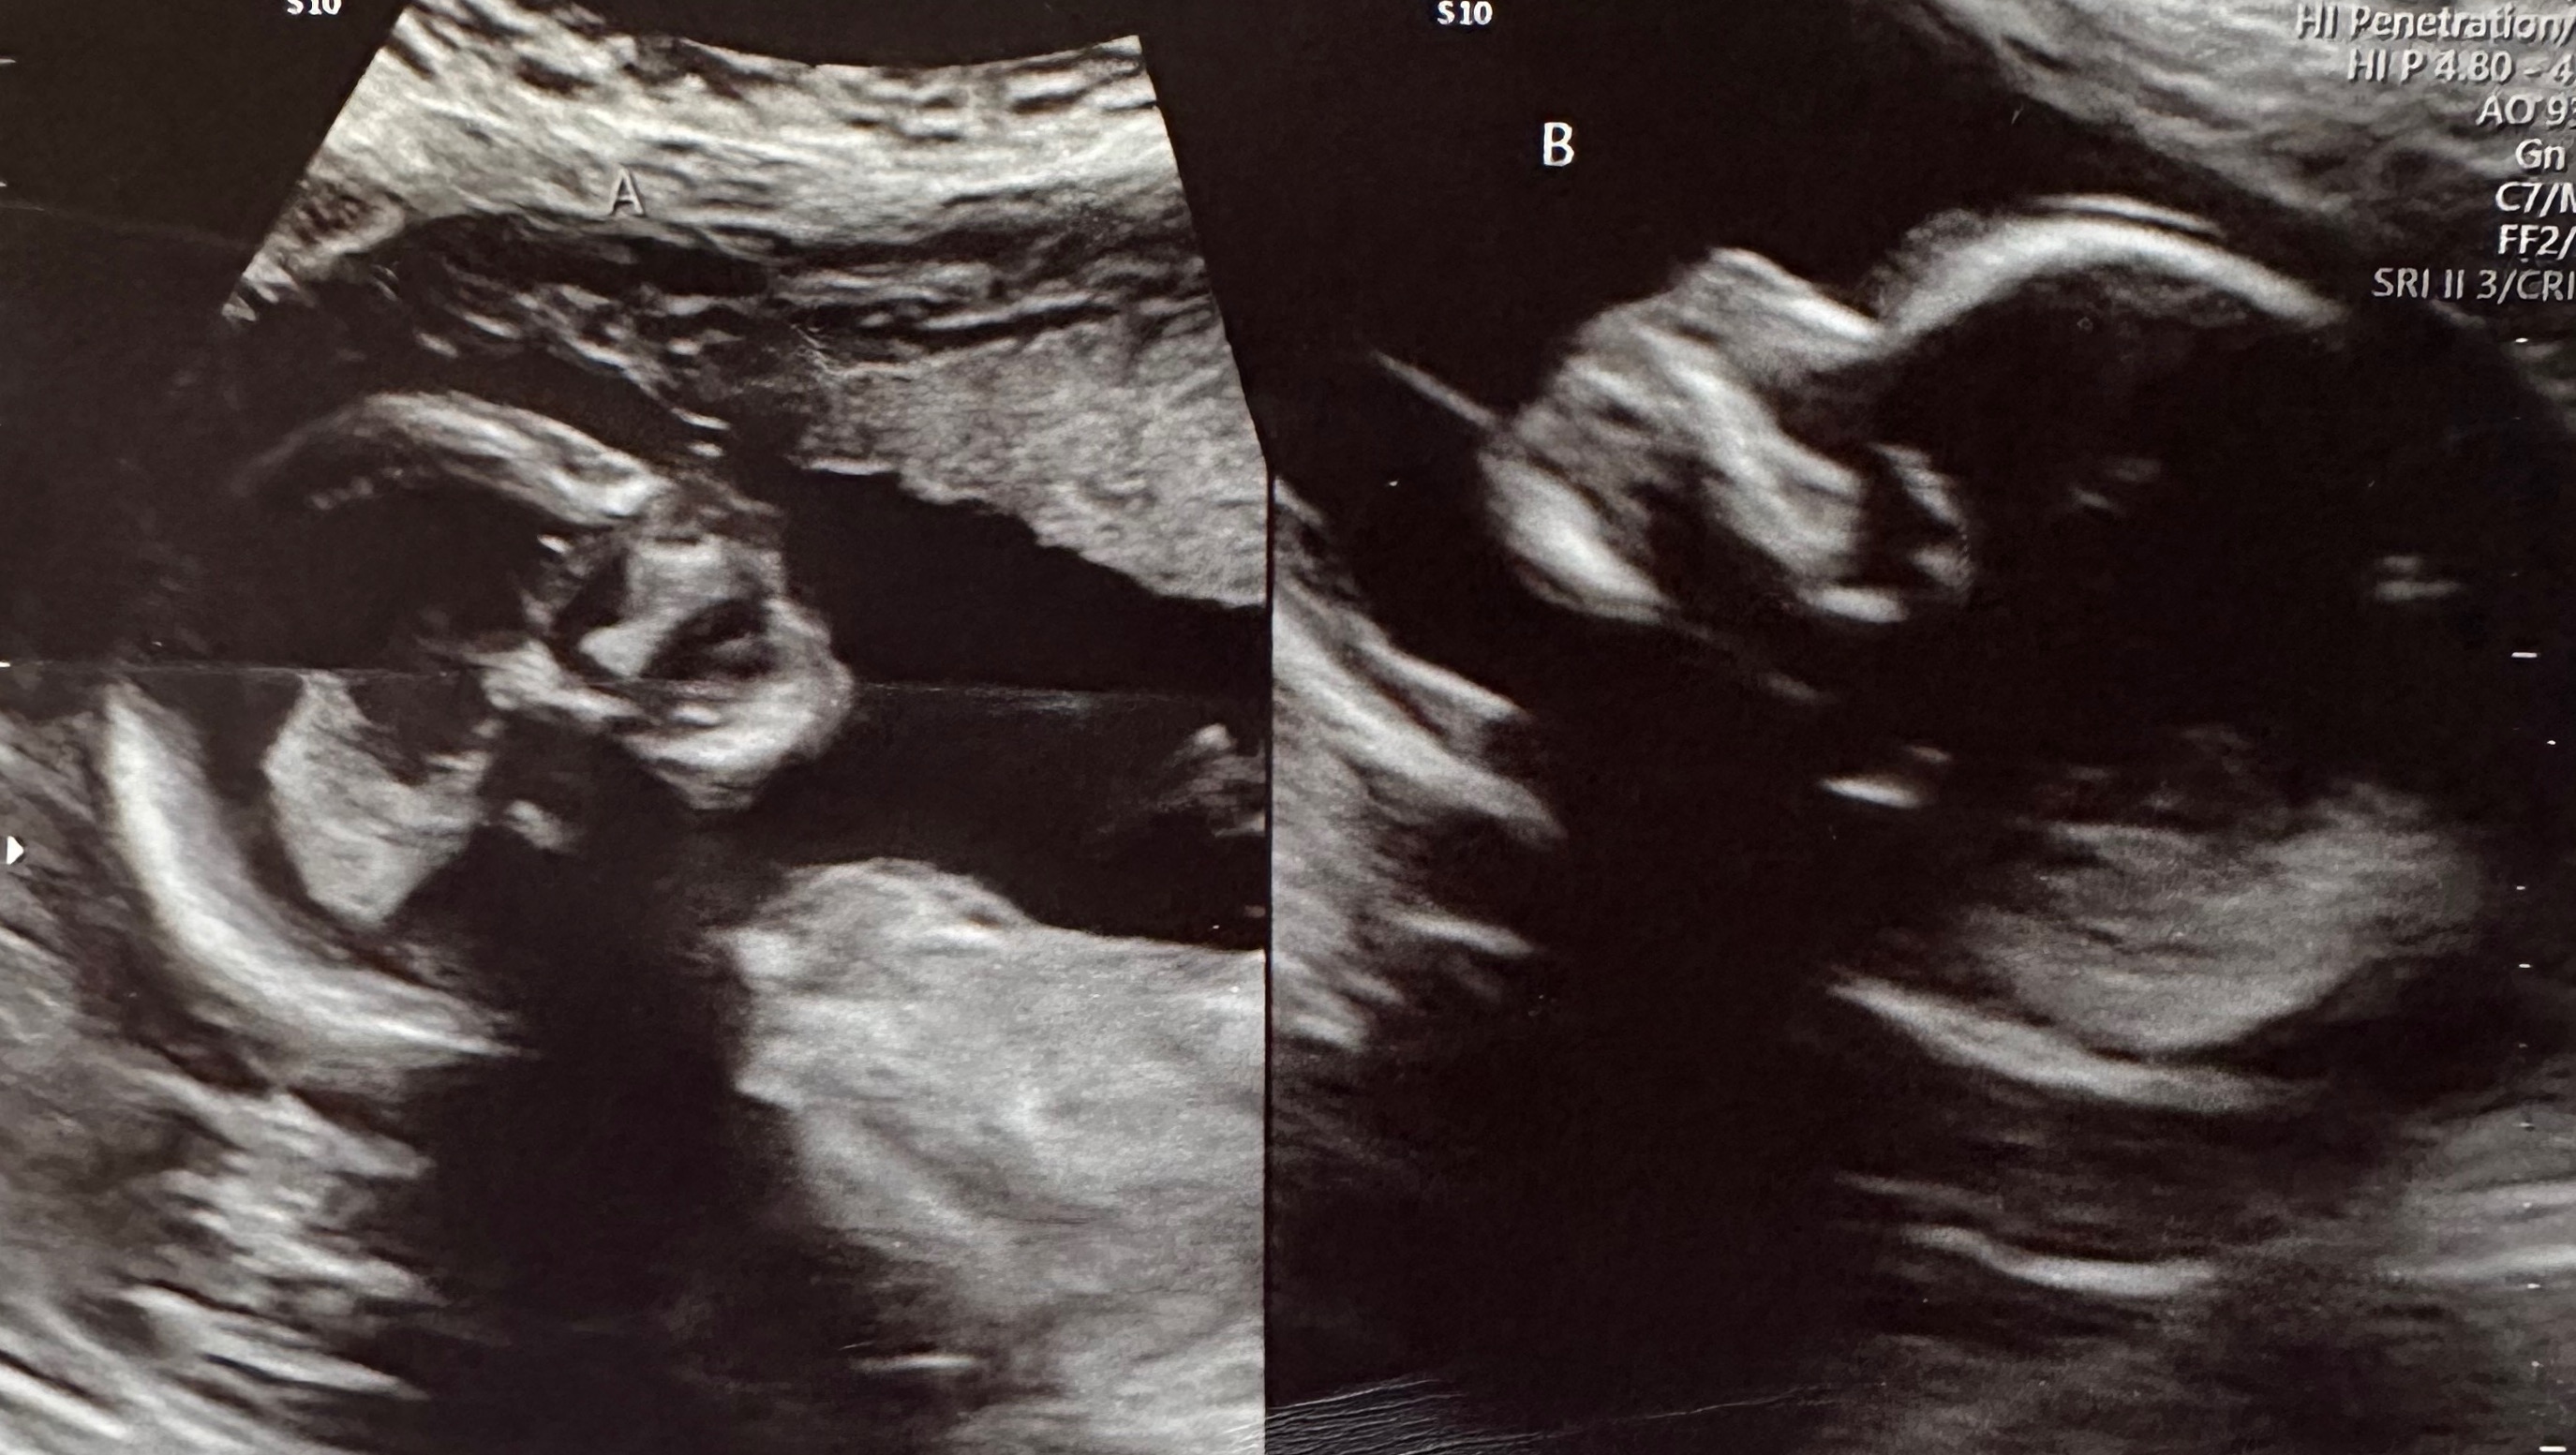

Caleb and Kelsey are currently pregnant with twins, with a 1 in 50 million chances pregnancy! Kelsey has a didelphic uterus, two separate uteri and two cervices, with a baby in each.